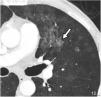

High-resolution computed tomography (HRCT) is the imaging method of choice for the evaluation and diagnosis of interstitial lung diseases because it confirms the presence of lung disease and establishes the correct diagnosis for associated complications. Nevertheless, the definitive diagnosis of these entities requires the imaging findings to be interpreted together with their clinical manifestations and histological confirmation. In this group of diseases, HRCT findings play a fundamental role, being especially important for avoiding unnecessary biopsies. For these reasons, clinicians need to be familiar with the basic radiologic patterns associated with this group of lung diseases: septal, reticular, nodular, ground-glass, cystic, and consolidations. This chapter describes the features of these patterns and ways that they can present, and it reviews some of the most common interstitial lung diseases, emphasizing the predominant radiologic patterns in each of them.